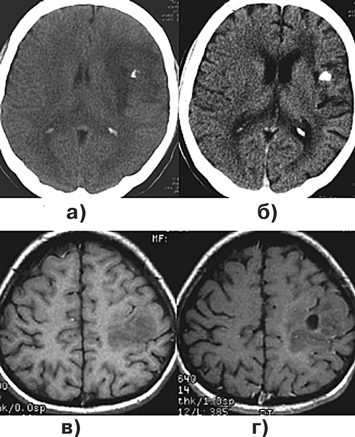

На МР-томограммах АА чаще выглядит как слабо отграниченное образование, имеющее гетерогенный сигнал как на Т1-, так и на Т2-изображениях. На Т1-взвешенных МРТ выявляются участки смешанной изо— и гипоинтенсивности сигнала (рис. 3а), на фоне которых могут наблюдаться геморрагические очаги с типичным повышением интенсивности сигнала. На Т2-взвешенных МРТ опухоль имеет вид обширной зоны гетерогенного повышения интенсивности сигнала (рис. 3б). В центральных отделах опухоли могут выявляться очаги кистозного перерождения. В этом же режиме лучше оценивается перитуморозный отек, имеющий повышенный сигнал и характерную форму в виде расходящихся лучей. При опухоли больших размеров и/или выраженном отеке обычно определяется значительный “масс-эффект”. Для большинства АА типично интенсивное усиление сигнала после введения контраста, хотя могут встречаться опухоли без накопления контрастного вещества (и без перитуморозного отека). Распространение по трактам белого вещества, происходящее в большинстве случаев при АА, приводит к тому, что биопсия обнаруживает опухолевые клетки в участках мозга, располагающихся вообще вне зоны накопления контраста и вне повышенного сигнала на Т2-взвешенных МРТ. Иногда отмечается распространение АА по эпендиме, мягкой оболочке и субарахноидальному пространству.

Рисунок 3. Анапластические астроцитомы:

а — анапластическая астроцитома правой темено-затылочной области (МРТ, Т1-взвешенные изображения; б — анапластическая астроцитома правой темено-затылочной области (МРТ, Т2-взвешенные изображения); в — глиобластома правой височной области, распространяющаяся на подкорковые узлы (МРТ, Т1-взвешенные изображения); г — лиосаркома правой теменной области (МРТ, Т1-взвешенные изображения)

На КТ плотность опухоли весьма гетерогенна (рис. 4а). Центральная зона низкой плотности представляет некроз, выявляемый в 95% случаев. Границы опухоли нечеткие. Петрификаты встречаются редко. Часто определяются кровоизлияния различной давности. Опухоль обычно окружена зоной перифокального отека, распространяющегося в белом веществе больших полушарий. ГБ обычно активно накапливают контраст. Усиление после введения контрастного вещества выражено часто неоднородно, контрастирование имеет характерный вид кольца с неоднородным внутренним контуром. В ряде случаев ГБ отсутствует узловой компонент, и опухоль растет инфильтративно, широко поражая полушарие. Рентгенологически признаки повреждения ГЭБ (накопление контраста) при этом нередко отсутствуют, и контрастное усиление мало изменяет характеристику сигнала от опухоли.

МР-проявления ГБ в целом отражают патоморфологические изменения, демонстрируя значительную гетерогенность опухоли. На Т1-взвешенных томограммах выявляется плохо отграниченное объемное образование со смешанным (изогипоинтенсивным) сигналом, центральным некрозом, которому соответствует сниженный по отношению к опухолевой массе сигнал (рис. 3в, 4в). На Т2-взвешенных изображениях выявляются участки гипо-, изо-, гиперинтенсивного сигнала от стромы ГБ, зоны некроза, кист и кровоизлияний. Выраженный “масс-эффект” и распространенный отек белого вещества часто сопровождают и небольшие по размерам опухоли (рис. 4б). Границы опухоли сливаются с перифокальным отеком.

Рисунок 4. Глиобластома правой височно-теменной области, распространяющаяся на подкорковые узлы:

а — КТ с контрастным усилением; б — МРТ, Т2-взвешенные изображения; в — МРТ, Т1-взвешенные изображения, с контрастным усилением; г — каротидная АГ

Так как ГБ часто бывают сильно васкуляризованы (рис. 4г), то на МР-томограммах, особенно Т2-взвешенных, могут выявляться сосуды опухоли (рис. 4б). В 5% наблюдений встречаются множественные ГБ (рис. 5в), для дифференциального диагноза с метастазами необходима стереотаксическая биопсия.

Рисунок 5. Примеры роста и распространения глиобластомы (МРТ, Т1-взвешенные изображения с контрастным усилением, аксиальная проекция):

а — "передняя бабочка" — глиобластома медиальных отделов обеих лобных долей, больше слева и колена мозолистого тела; б — "задняя бабочка" — глиобластома медиальных отделов теменно-затылочных с обеих сторон, больше справа и валика мозолистого тела; в — первично-множественный рост глиобластомы; г — перивентрикулярное распространение глиобластомы, больше вокруг передних рогов обох боковых желудочков

Учитывая гетерогенность строения, Т1 и Т2-взвешенные МР-томограммы выявляют негомогенную опухоль (рис. 3г). В ней часто наблюдается некроз и кровоизлияния. После введения контрастного вещества обычно отмечается гетерогенное усиление сигнала от опухоли. На основе МР-характеристик ГС невозможно дифференцировать от ГБ.